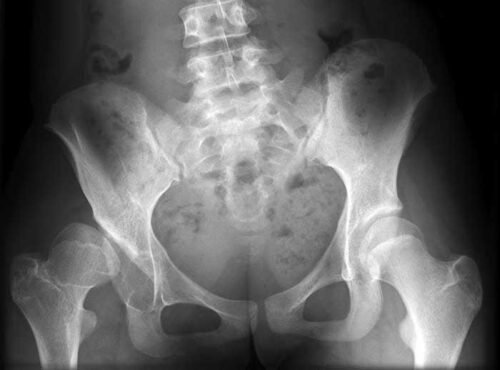

- خشونة مفصل الفخذ. والتى حدث بها تلف شديد بغضاريف المفصل، وكلما تأخر المريض في تلقي علاج الخشونة، كلما تطورت درجة الإصابة وتلفت عظام المفصل. كذلك إذا لم يستجب المريض للعلاج الدوائي، وكان الألم شديدًا بدرجة تؤثر على أسلوب الحياة الذى يتمناه المريض.

- التعرض لكسر في المفصل نتيجة لسقوط أو التعرض لحادث أو إصابة قوية.

- كسور عنق عظمة الفخذ لدى كبار السن. وسببها الرئيسي هشاشة العظام.

- نكروز رأس عظمة الفخذ. وهو حالة مرضيه سببها نقص التروية الدموية للمفصل. مما يؤدي إلى تآكل وتسطح رأس عظمة الفخذ.

- التهاب المفصل الإنتاني. والذي ينتج عن حدوث عدوى بكتيريه أو فيروسيه, أو عن طريق الجراثيم التي تنتقل عبر مجرى الدم من جزء آخر من الجسم. كذلك عند التعرض لإصابة نافذة، مثل عضة حيوان أو إصابة جسدية نقلت العدوى مباشرةً إلى المفصل.

- التهاب المفاصل الروماتويدي. وهو مرض مناعة ذاتيه، حيث يهاجم الجهاز المناعي أحد مفاصل الجسم. وعادة ما تكون مفاصل اليد ونادرًا ما تنتقل للحوض.

- خلل التنسج العظمي. وهو خلل في نمو الخلايا الليفيه مما يؤدي إلى نمو العام بشكل ضعيف وأكبر من الحجم المعتاد.